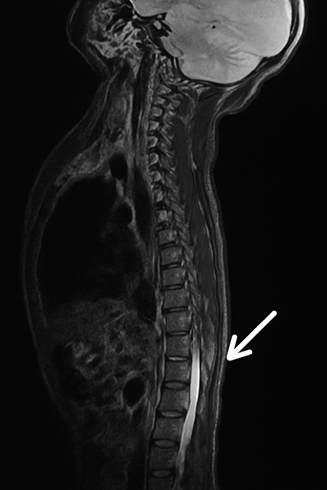

İncelememizin merkezinde, öğrencilerimden biri tarafından tarafıma iletilen, yeni doğmuş bir bebeğe ait Spinal MRI (Manyetik Rezonans Görüntüleme) yer almaktadır. Bana ilettiği görüntünün sagittal düzlemde olması çok manidar. Çünkü biliyorsunuz tıbbi görüntülemelerde sagittal, vücudu sağ ve sol olarak ayıran düzlemde yan görüntüleme olarak geçer. Ayrıca coronal; önden ve transverse (axial) yani yatay olarak da görüntü alınabilir ama bana görüntü sagittal olarak geldi. Kelime kökenine dikkat etmenizi istiyorum.

Tabii ki bu kelime kökü astrolojide kullandığımız Sagittarius (Yay) burcunu da işaret ediyor ki anlam olarak oku atan figür olarak karşımıza çıkıyor. Eşzamanlılık yine konuşuyor. Dikkat ederseniz şu an transit Güneş’in Yay burcunda dolandığı günlerdeyiz. Doğum anı transiti de zaten Yay burcunda birçok gezegenin stelyum oluşturduğu (Merkür, Venüs, Güneş, Mars) bir zamanı işaret ediyor. Tüm bunlar çok manidar…Görsel, hasta gizliliğini korumak amacıyla değiştirilmiştir ve yalnızca örnekleme amacıyla kullanılmıştır.

Tüm göstergeleri bir arada değerlendirdiğimizde, doğum haritasının genelinde denge, eksen, sınır ve kapanma temalarının belirgin biçimde öne çıktığını gözlemliyoruz. Özellikle dikkat çeken nokta da omurganın belirli segmentlerinde yapısal kapanmanın tamamlanmamış olmasıdır. Görsele dikkat edin. Klinik görüntülemede, anomalinin torakolomber geçiş bölgesinde, yaklaşık olarak T10–T11 seviyesinden başlayıp L1–L2 segmentlerine kadar uzanan bir alanı kapsıyor. Bu bölgede vertebral arkların tam olarak kapanmadığı ve omurilik dokusunun ilgili segmentlerde vücut dışında açık şekilde kaldığını gözlüyoruz.

Omurganın segmental yapısında hem modern tıpta hem de medikal astroloji geleneğinde belirli vertebra seviyelerinin bazı organ ve sistemlerle fonksiyonel ilişkiler kurulmaktadır. Torakal ve lomber vertebraların; böbrekler, üreterler, otonom sinir sistemi dalları ve pelvis bölgesiyle ilişkili refleks alanları açısından ilişkili olduğunu kabul ediyoruz. Özellikle T10–L2 segmentlerinin, renal fonksiyonlar, üriner sistem ve abdominal–pelvik geçişle bağlantılı sinir ağlarının geçtiği bir bölge olarak tanımlandığını görüyoruz (Gray’s Anatomy; Netter, Atlas of Human Anatomy).